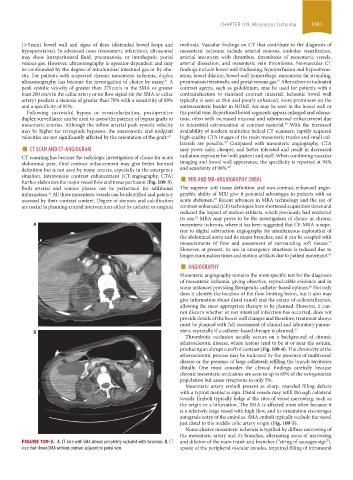

FIGURE 109-3. A. CT slice with SMA almost completely occluded with thrombus. B. CT and dilation of the main trunk and branches (“string of sausages sign”),

slice that shows SMA without contrast adjacent to portal vein. spasm of the peripheral vascular arcades, impaired filling of intramural